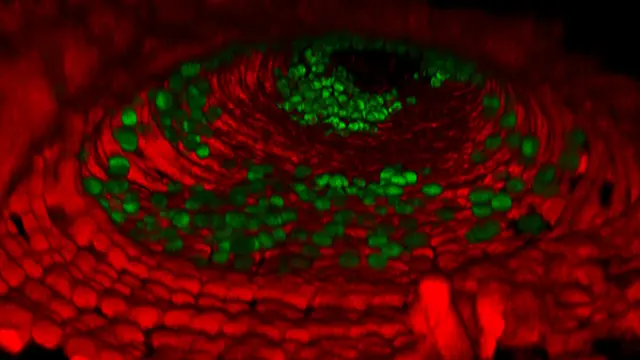

Científicos del 'Francis Crick Institute', financiados en parte por el Cancer Research de Reino Unido, han descubierto cómo un interruptor genético implicado en el empaquetamiento del ADN puede ser clave para la capacidad de una célula de cáncer de seguir creciendo. En concreto, encontraron que la producción de una proteína llamada H1.0 se apaga con frecuencia en muchos tipos de cáncer y que la reactivación de esta proteína detiene el crecimiento del tumor.

Mediante el estudio de las células cancerosas que carecen de H1.0, encontraron que el ADN se desenrolla en puntos clave, activando una serie de genes que detienen la célula en un estado 'inmaduro'. Esto permite que las células continúen con la división y la expansión del tumor.

Pero a medida que el tumor crece, H1.0 puede llegar a ser espontáneamente encendida en algunas células. Los investigadores vieron que esta nueva región del ADN actúa como el interruptor de control para la producción de H1.0. Con H1.0 volviendo a funcionar, se bloquean de nuevo los genes necesarios que necesita la célula para seguir creciendo, volviendo a una vida útil finita normal.